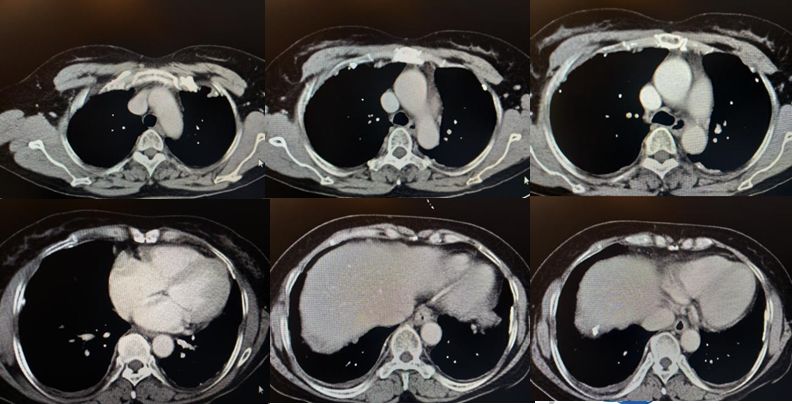

图示:2018-11-27胸部CT影像

•入院后查血肿瘤标志物正常,T-SPOT阴性。胸部CT见两肺内少许絮索条影,两侧胸膜结节状增厚伴散在钙化。

图示:患者两侧胸膜可见结节、钙化影(白箭)

到目前为止,除了胸腔积液之外,仔细阅读该患者胸部CT发现该患者的另外一个特点就是胸膜增厚、结节、钙化影。通过这一线索,不排除有胸膜来源疾病的可能。